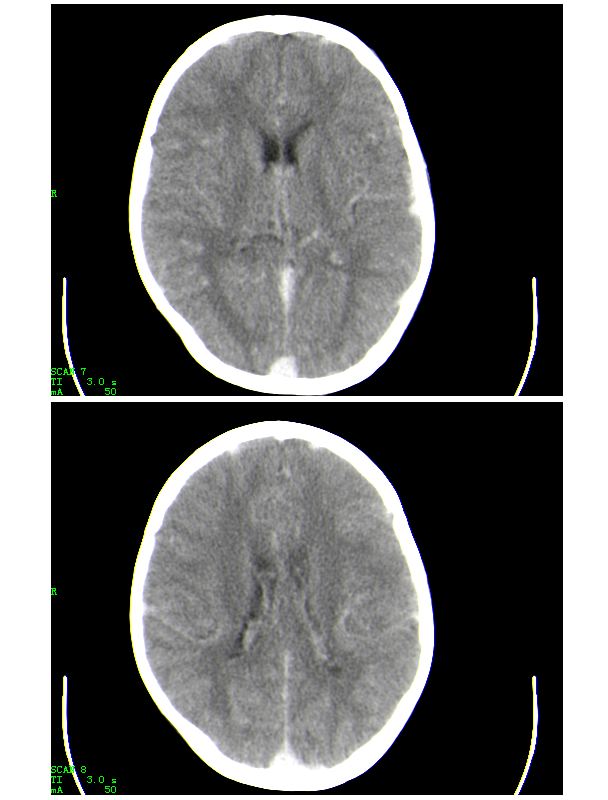

下面是第二天的复查和受伤后第五天的复查,左侧硬膜下血肿有所吸收,脑内条状高密度无改变

作者: hhcckk    时间: 2009-12-9 03:52

标题: 回复:ct23482:头颅外伤,大家看看